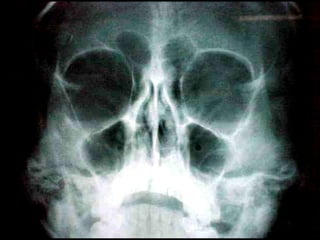

Mucormicosis

ntroducción.

Con este término, nos referimos a un grupo de micosis causadas por hongos

del orden Mucorales. La mayoría de los casos se presenta en personas con

factores de oportunismo severos como diabetes mellitus descompensada,

leucemia, o cáncer. Son infecciones graves que pueden causar la muerte; las

variedades clínicas más frecuentes son: rinocerebral, pulmonar, digestiva y

cutánea primaria. Las infecciones causadas por hongos del orden Mucorales,

generalmente se adquieren por vía respiratoria ya que las esporas de los

hongos se encuentran en el ambiente, aunque en las formas cutáneas

primarias, la infección se adquiere por solución de continuidad.

Dr. Luis J. Méndez Tovar

Unidad de Investigación Médica, Hospital de Especialidades C.M.N. Siglo XXI.

La paciente falleció a las 24 horas de internamiento por trombosis del seno

cavernoso.